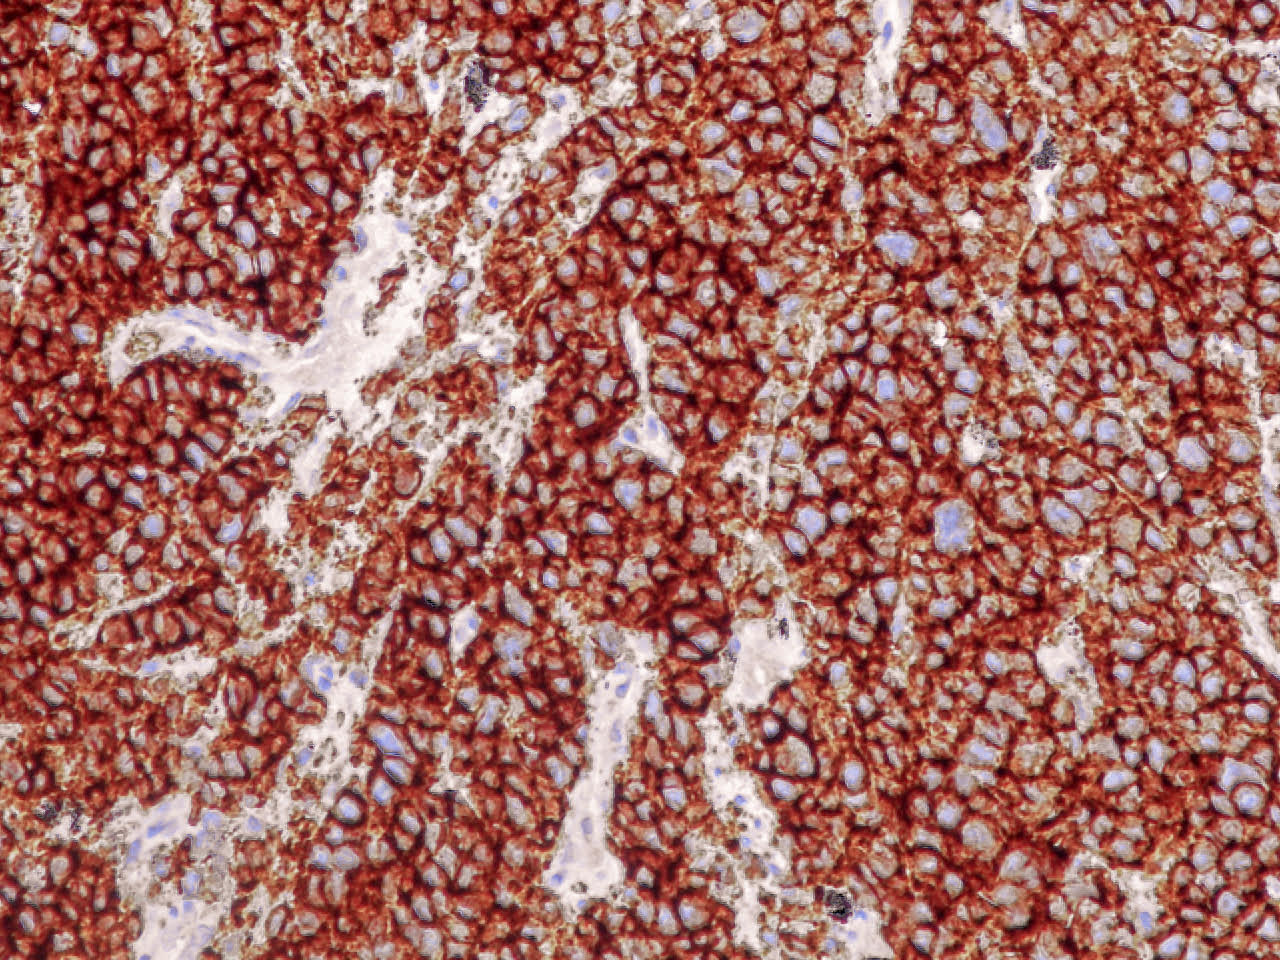

Microscopic (histologic) images

Contributed by Ioanna Abba Nteka, M.D., Aggeliki Cheva, M.D., Ph.D., Antonia Loukousia, M.D., Roseann Wu, M.D., M.P.H. and Kyriakos Chatzopoulos, M.D., Ph.D.

Positive stains

- Neuroendocrine markers, usually at least 2 focal to diffuse (chromogranin, synaptophysin, CD56), caution if CD56 is the only neuroendocrine marker expressed

- Cytokeratins AE1 / AE3, CAM5.2

- High Ki67 (40 - 80%) helpful to differentiate from carcinoid tumors, especially in small biopsies (Semin Diagn Pathol 2015;32:469)

- Comment: Multiple sections from the biopsy material reveal an infiltrative malignant tumor consisting of large cells with abundant amphophilic cytoplasm and large, ovoid or round nuclei with prominent nucleoli and increased mitotic activity. Tumor cells form solid nests with peripheral palisading and central necrosis. Immunostains performed on paraffin sections show diffuse and strong expression of keratins AE1 / AE3, synaptophysin, chromogranin, CD56 and nuclear expression of TTF1 and ISNM1. No expression of p40 or napsin A is seen. These findings support the diagnosis.